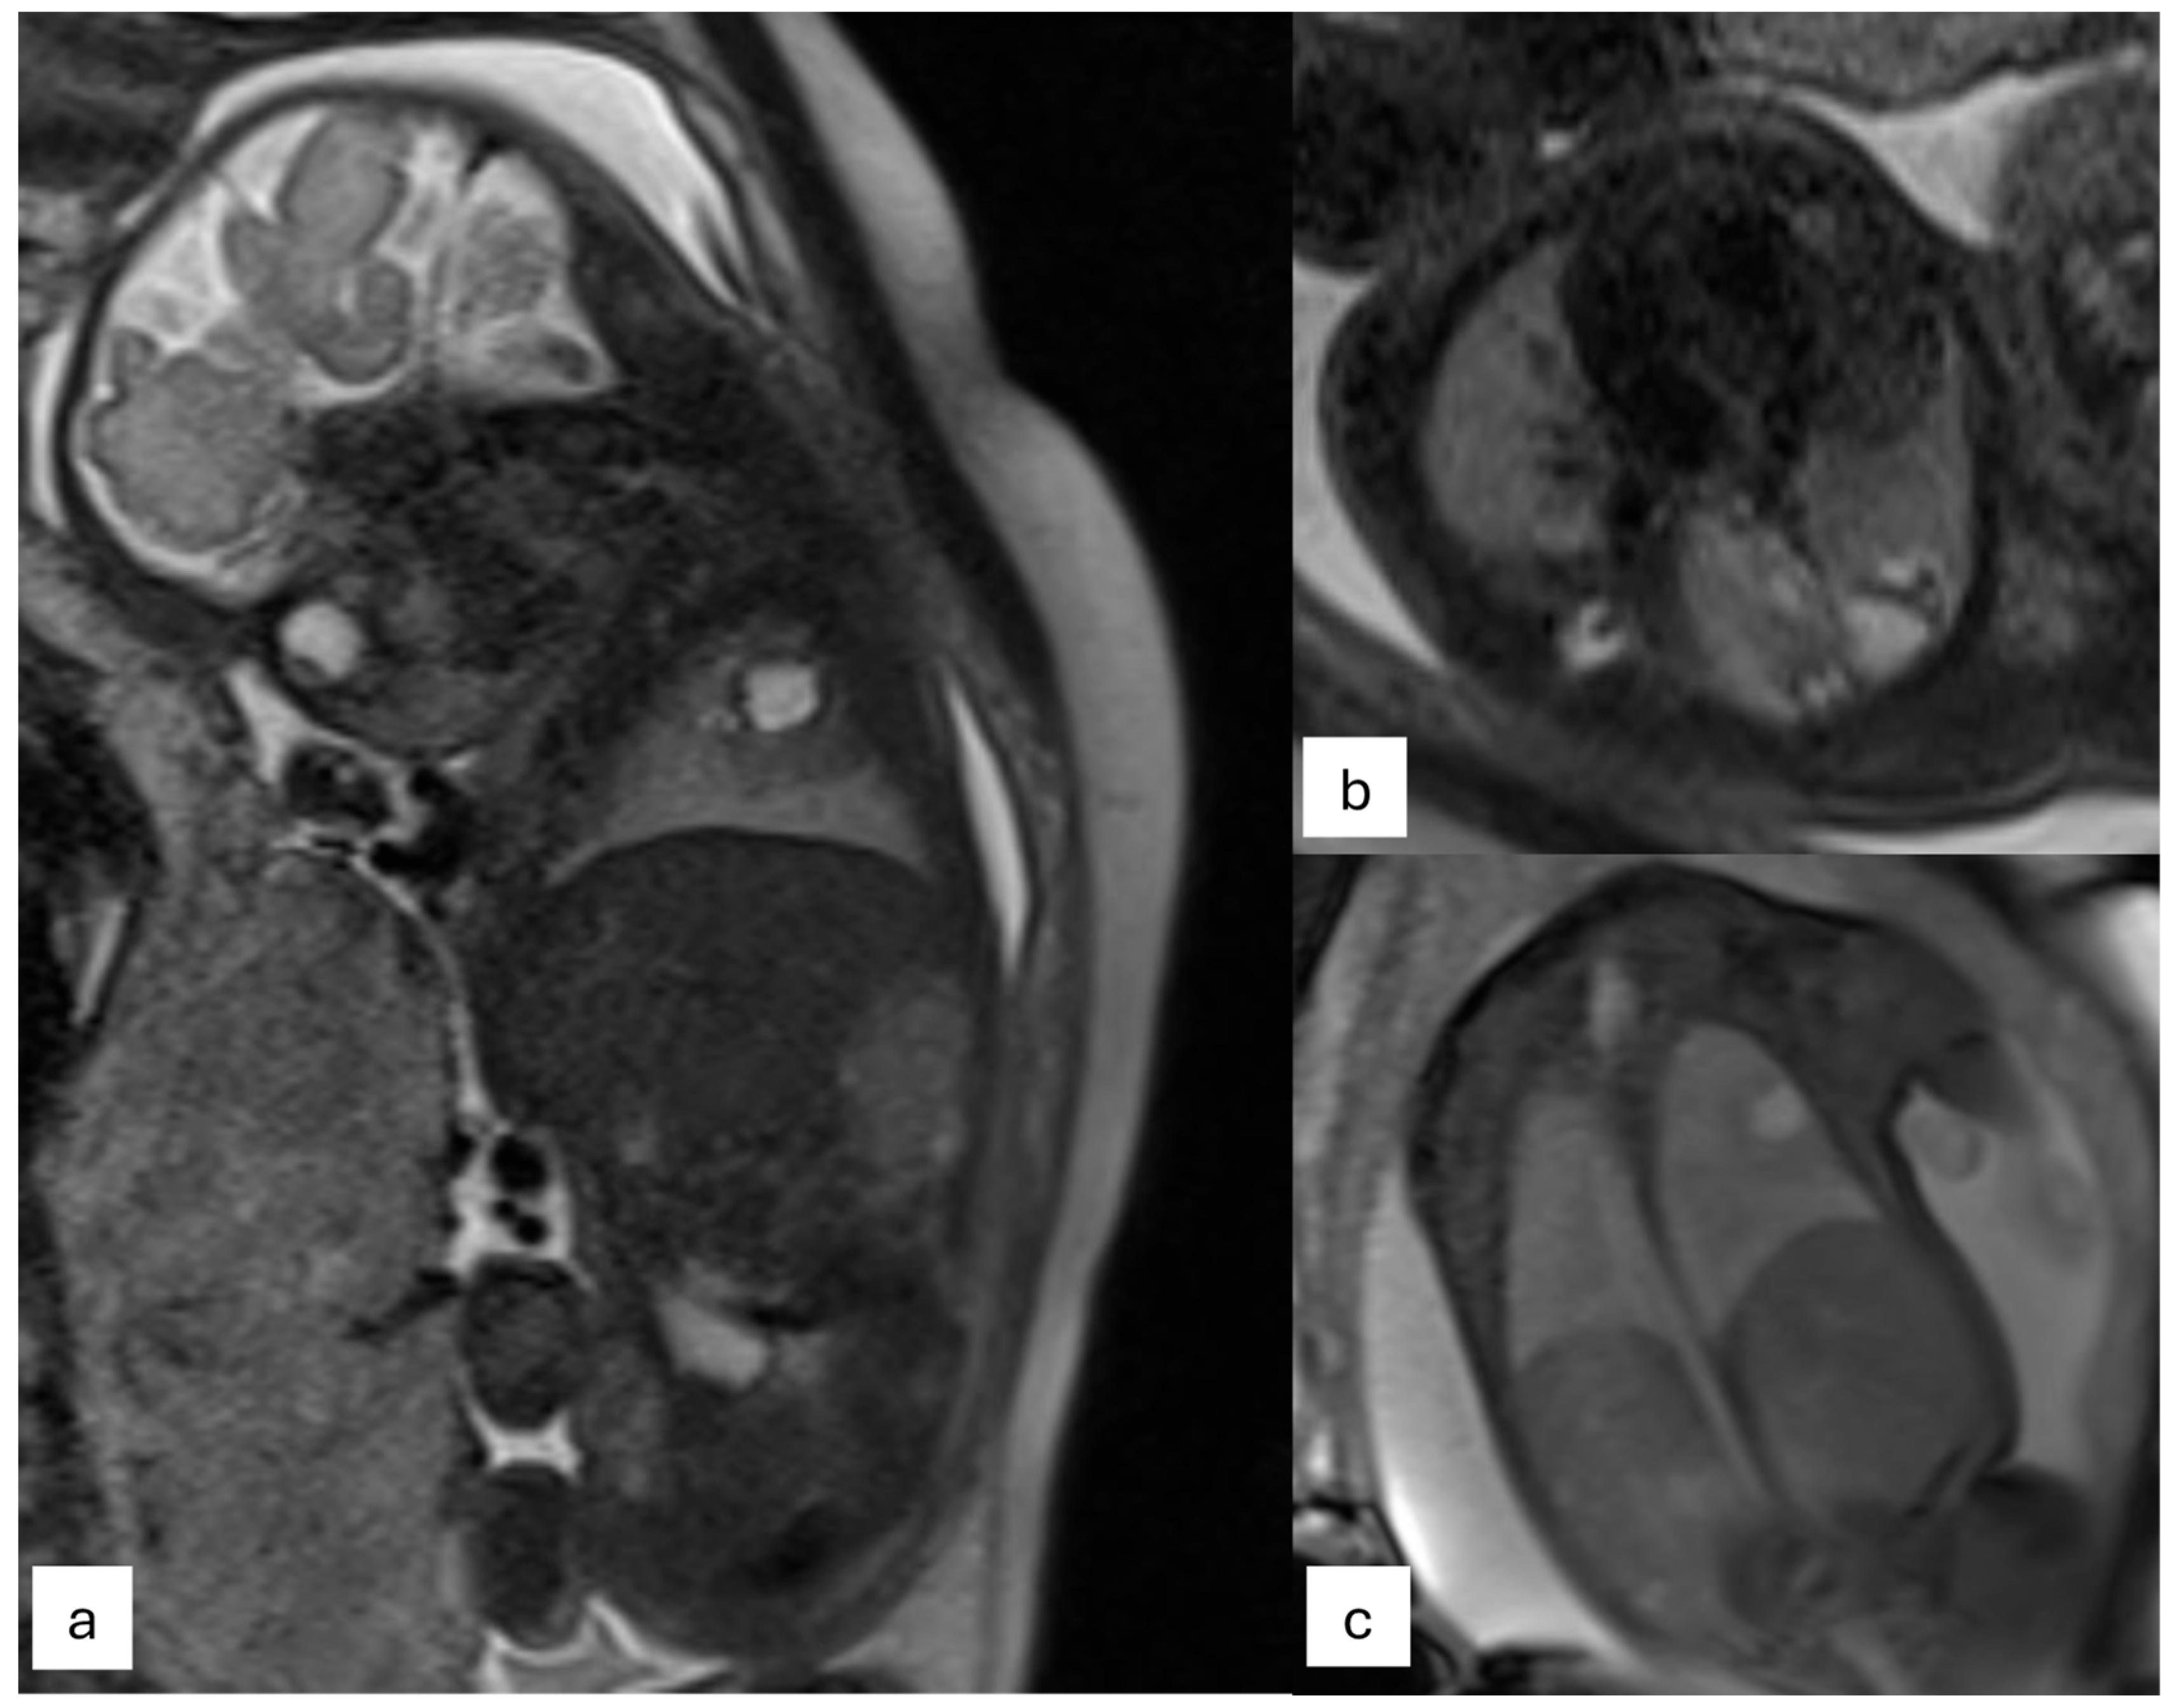

- CPAM: This is the most frequent malformation, consisting of communication with the normal tracheobronchial tree. They can present in solid or cystic form and are classified into 5 subcategories (Figure 2).